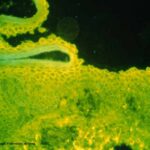

IF Testing. DIF testing of perilesional skin is positive in the vast majority of cases. Two patterns of pemphigus antibody deposition have been described. In most cases, there is full-thickness squamous intercellular substance deposition of IgG. Rarely, IgG may be localized only to the superficial portion of the epidermis . IIF testing of serum reveals |

squamous intercellular substance deposition of IgG in 80% to 90% of cases. |